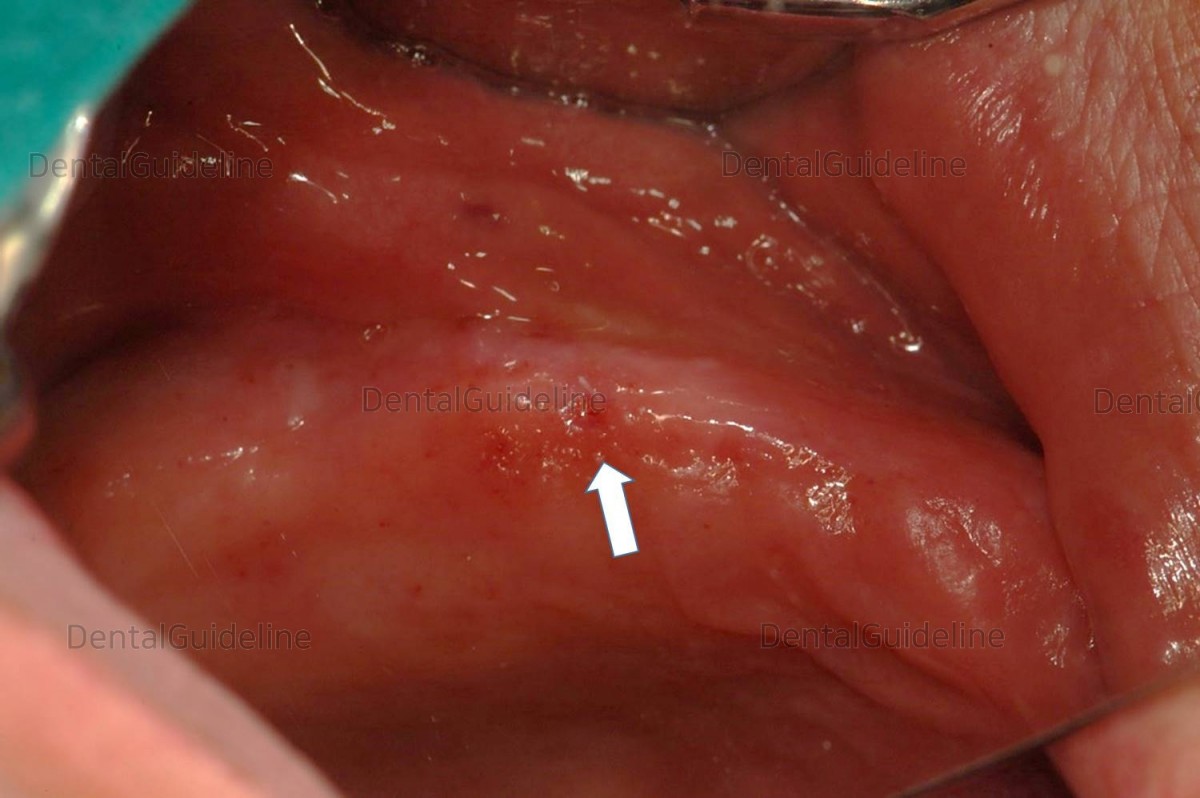

10 days after implant placement.